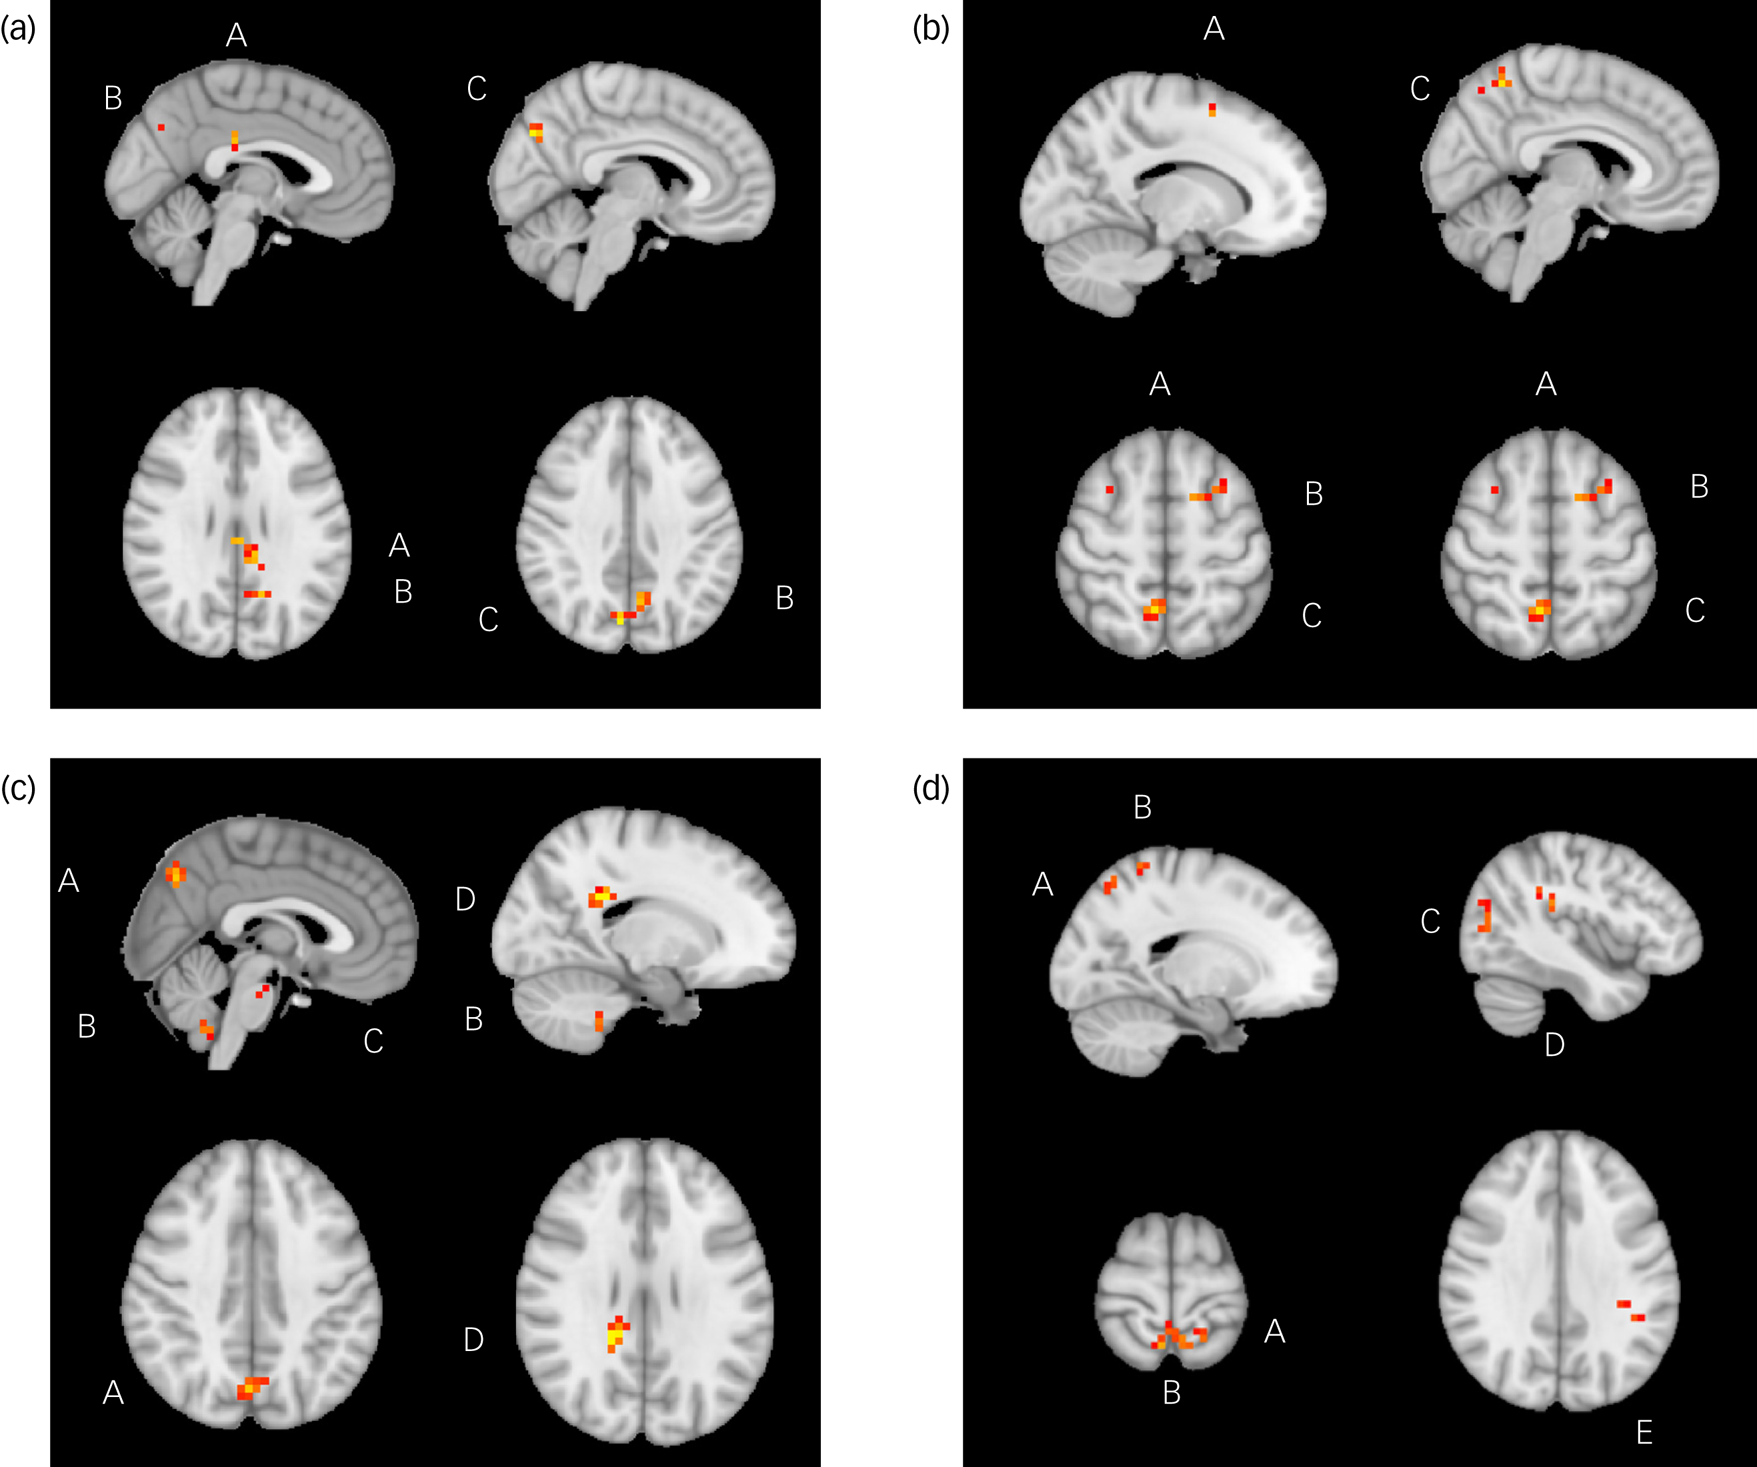

There was a positive correlation between change in DARS score from week 8 to week 16 and week 8 rsFC between the ACC (which was used as the seed) and the posterior cingulate cortex (PCC) (P = 0.03), as well as the bilateral ventral-posterior praecuneus (P = 0.01) at week 8. Change in DARS score was also negatively correlated with week 8 rsFC between the ACC and right dorsal-anterior praecuneus (P = 0.03), middle frontal gyrus (left: P = 0.004; right: P = 0.02) and left superior frontal gyrus (P = 0.004).

Change in DARS score from week 8 to week 16 was also positively correlated with week 8 rsFC between the NAc (which was used as the seed) and bilateral ventral-posterior praecuneus (P = 0.001), cerebellum lobule IX (P < 0.001), pons (P = 0.01) and splenium of the corpus collosum (P = 0.03). Change in DARS score was negatively correlated with week 8 rsFC between the NAc and left supramarginal gyrus (P = 0.02), parietal operculum (P = 0.02), middle occipital gyrus (left: P = 0.004; right: P = 0.01), superior parietal gyrus (P < 0.001) and bilateral dorsal-anterior praecuneus (P < 0.001). All results are presented in Table 2, and presented visually in Fig. 1.

Fig. 1 Significant relationships between change in Dimensional Anhedonia Rating Scale (DARS) score and resting-state functional connectivity (rsFC), week 8 to week 16. (a) There were significant positive relationships between change in DARS score and rsFC between the anterior cingulate cortex and posterior cingulate cortex (A), left praecuneus (B) and right praecuneus (C). (b) There were significant positive relationships between change in DARS score and rsFC between the between the anterior cingulate cortex and superior frontal gyrus (A), middle frontal gyrus (B) and right praecuneus (C). (c) There were significant positive relationships between change in DARS score and rsFC between the nucleus accumbens and praecuneus (A), cerebellum lobule IX (B), pons (C) and splenium of corpus collosum (D). (d) There were significant positive relationships between change in DARS score and rsFC between the nucleus accumbens and superior parietal gyrus (A), praecuneus (B), middle occipital gyrus (C), parietal operculum (D) and supramarginal gyrus (E).